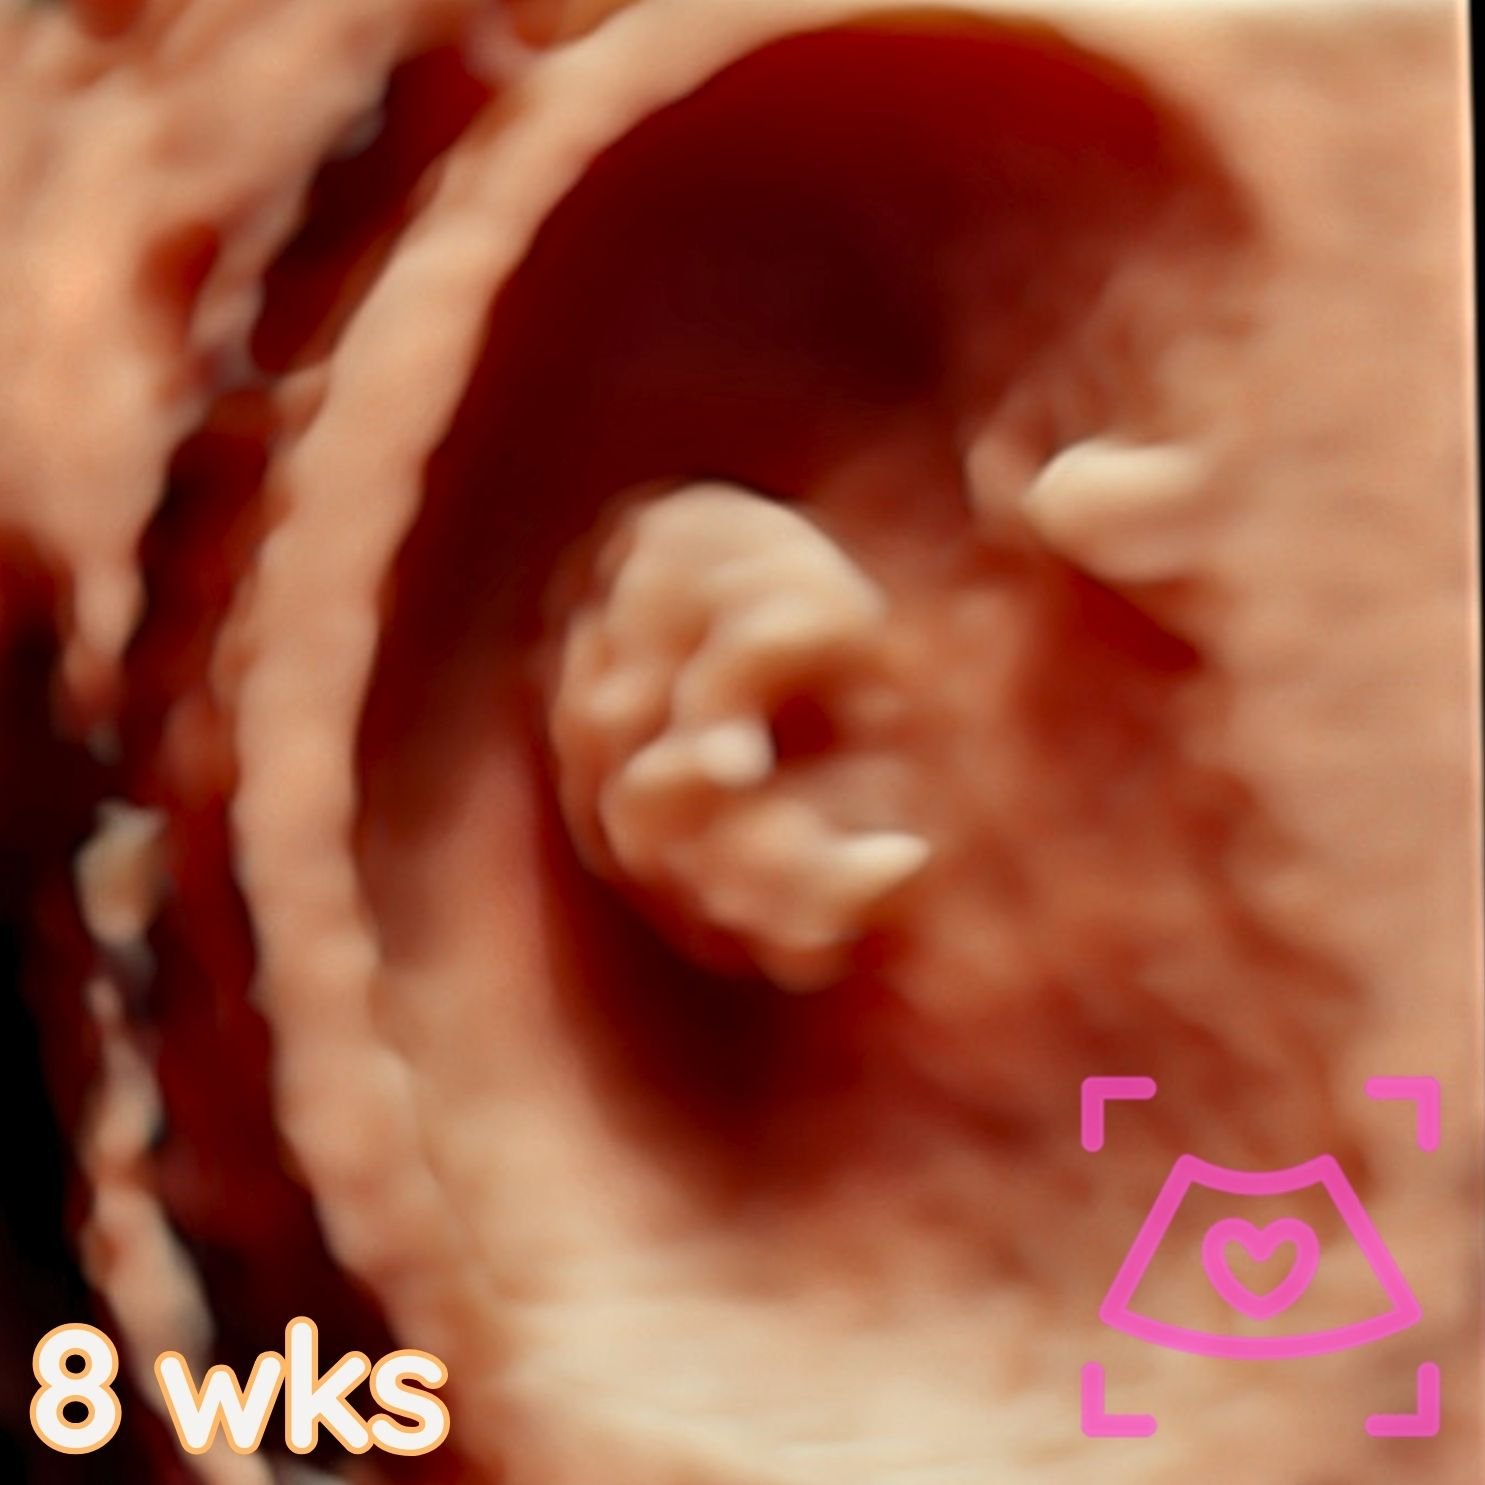

All ultrasounds at this facility are performed abdominally (on top). See examples below from 5-40 weeks! Recommended times can be found on the Services Page and when booking.

1st Trimester